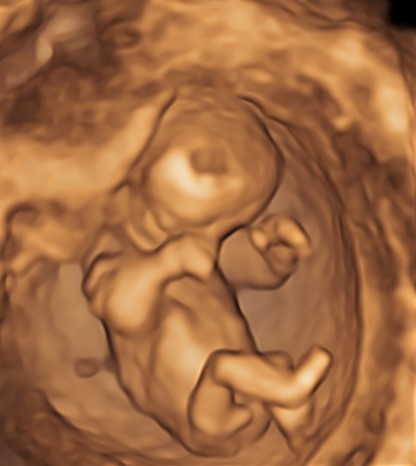

Indipendentemente dalla nostra scelta, è di capitale importanza fare comunque una ecografia fra la 11° e la 13° settimana. Infatti già a questa epoca gestazionale siamo in grado di condurre un’iniziale valutazione morfologica. Ma soprattutto questo è la finestra di opportunità per studiare la translucenza nucale. In realtà questa ampia finestra di tre settimane ha il suo momento più favorevole a 11 settimane e mezza e inizio dodicesima.

Si va a misurare quindi attraverso una ecografia lo spazio dietro la nuca: è una fisiologica raccolta di linfa che tende ad aumentare in diverse situazioni patologiche risultando essere un indice generale di buon andamento della gravidanza dove più è sottile più siamo tranquilli a riguardo di patologie cromosomiche, malformazioni cardiache, ed alcune malattie genetiche.

In questi 4/5 centimetri la risoluzione degli apparecchi moderni riesce a fare una prima valutazione morfologica, per vedere che ci siano tutti i “necessori” ed eventualmente anche accessori: cercando è possibile evidenziare il tubercolo genitale (sempre che il piccolo decida di essere collaborante e mostrare le proprie grazie). Si chiama così perché clitoride e pisellino hanno le stesse dimensioni a questa epoca, ma è possibile riconoscerli in base all’angolo rispetto al corpo: parallelo al corpo per le signorine, verso l’alto per i maschietti. Attenzione però la sensibilità, ovvero quanto ci azzecchiamo, è intorno al 60%.

La parte morfologica è molto importante, riusciamo a studiare l’estremo cefalico – a questa epoca il cervello fetale è molto semplice – , il massiccio facciale con occhi, naso bocca, le orecchie sono abbastanza facili da essere evidenziate. Nel torace oltre ai campi polmonari possiamo vedere il cuore battere ritmicamente e confermare la presenza delle quattro camere cardiache. Nell’addome riusciamo ad evidenziare lo stomaco e l’inserzione del cordone ombelicale. Si nota la presenza della vescica e del tubercolo genitale. Si possono esplorare tutti e quattro gli arti.

Per i genitori vedere sotto i propri occhi prendere forma il tesorino risulta una esperienza indimenticabile e impareggiabile al limite fra incredulità e la sorpresa come tutto sia già presente seppur in scala ridotta.